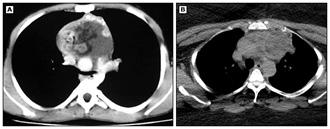

Figura 8.

(A) Una radiografía de tórax muestra una clavícula derecha rota con un gran neumotórax derecho y neumomediastino en una mujer de 24 años atropellada por un automóvil. (B) Una radiografía obtenida después de la colocación de un tubo torácico muestra un neumotórax persistente. Se observó una gran fuga de aire del tubo. La broncoscopia reveló una rotura completa del bronquio principal derecho